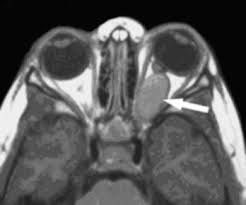

A neurological exam will typically show partial or total loss of vision or changes in the optic nerves. Increased pressure in the brain may be present. Other tests used to help diagnose optic nerve glioma include brain computed tomography (CT) scans, magnetic resonance imaging (MRI) of the brain, and biopsies.